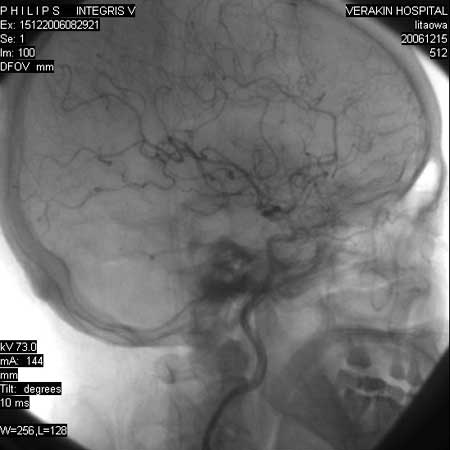

标题: DSA0063:颈内动脉血管造影

女,60岁,行全脑血管造影,图片较多,选了左颈内动脉造影100幅图中的10幅图片,请包涵。

支持后交通动脉起始部动脉瘤。

后交通动脉瘤.

另外:大家讨论的\"动脉瘤\"实际是血管分支重叠影像,本帖单侧颈内动脉仅见轻度动脉硬化性狭窄..参考旋转dsa请连接:http://www.sdhct.com.cn/radinet/read.php?tid=19818

头颈部旋转dsa技术是系统在开始曝光采集图像的同时,c形臂支架围绕患者做2次旋转运动,第1次旋转运动从注射对比剂后约2 s开始,获得一系列不同角度的含对比剂图像,称为对比像(contrast)。观察显示器,当病变血管的对比剂消失后,第2次旋转运动从对比像的结束位置开始,结束于对比像的起始位置,从而获得一系列减影所需的蒙片(mask),旋转dsa在采集实时图像时,以非减影方式显示,经过后处理,在回放时可分别得到相应角度的减影图像,清晰地显示血管解剖学的结构和形态。